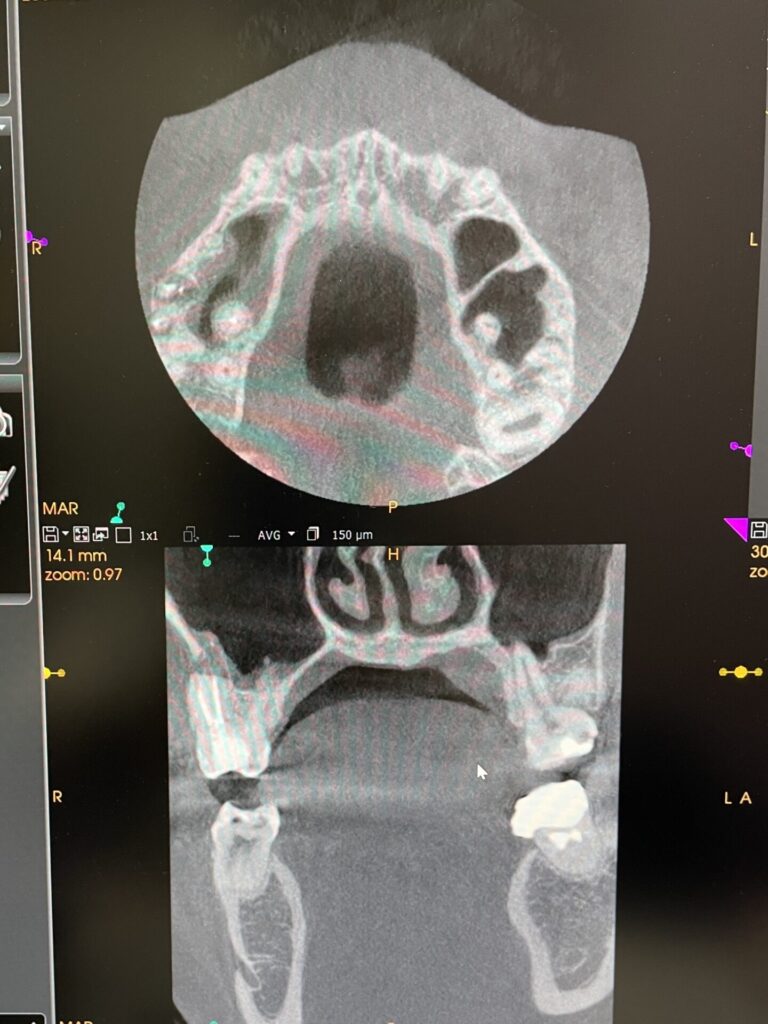

上の右奥の歯ぐきにニキビ様のものが出来ています。これもなかなか治らないとのことでした。デンタルレントゲンやCT検査の結果、大臼歯の根3本とも先端に膿がある状態でした。根管治療も中途半端な状態で仮の蓋が詰めてあるだけでした。

初診時のデンタルレントゲン・CT画像

ラバーダム防湿を行い、マイクリスコープ下での治療です。近心の根には2つの根管があります。この第2根管は裸眼の治療では高頻度で見落とされる傾向にあります。CTを事前に撮影しておくことで複雑な歯の神経の道を事前に把握することは非常に重要です。

第2根管までしっかりと根管充填が出来ていることがわかります。また上顎洞粘膜の腫れも軽減していることがわかります。